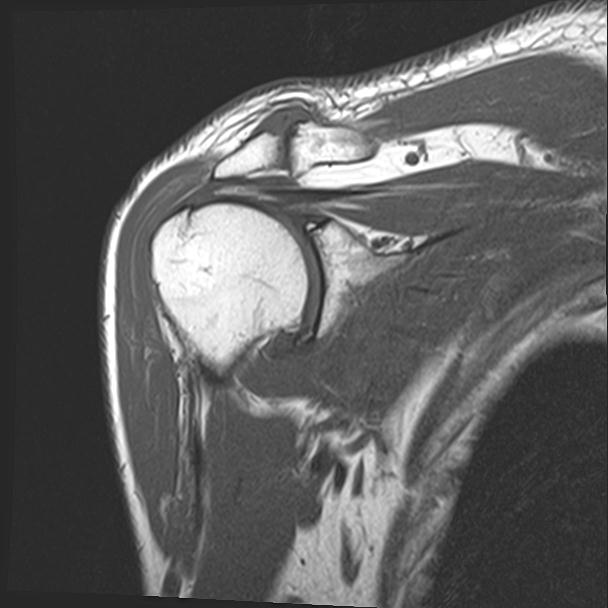

60058 3/9 11/4 右肩 2R+MRI 73歳男性 肩腱板損傷